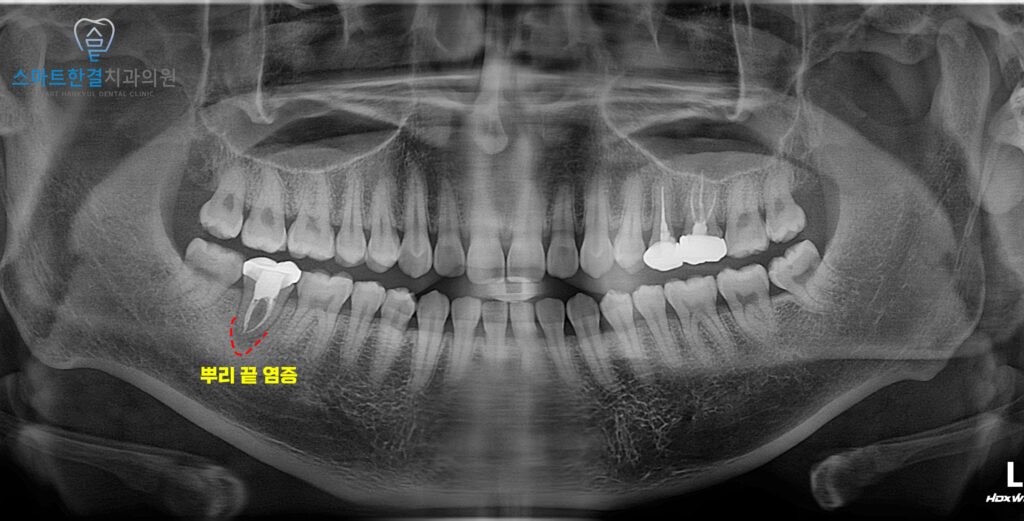

23.10.19

파노라마를 촬영하여 확인해 보니,

신경치료를 받았던 치아 뿌리로

염증이 잡혀있는 것을 확인할 수 있었어요.

신경치료를 진행한 치아에

다시 염증이 생기는 원인은 다양해요.

치아 뿌리 내부 구조가

매우 복잡해 초기 신경치료 시

미처 제거되지 않은 세균이 남아 있을 수 있고,

시간이 지나면서 보철물의 틈이나

미세한 균열을 통해 세균이

다시 침투하는 경우도 있어요.

또한 오래된 신경치료의 경우

치료 당시의 한계로 인해

감염이 완전히 차단되지 못해

뿌리 끝 염증으로 이어지기도 해요.